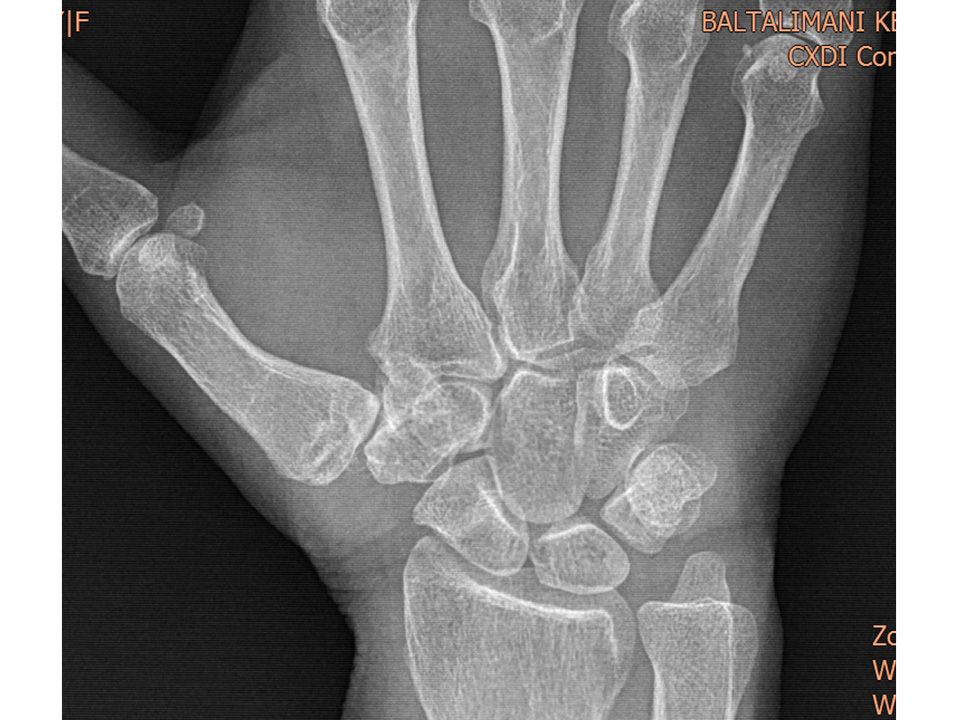

62 yaş, kadın, sağ el dominant10 yıldır her iki el başparmak CMC eklemde ağrıSağ tarafta grind test +